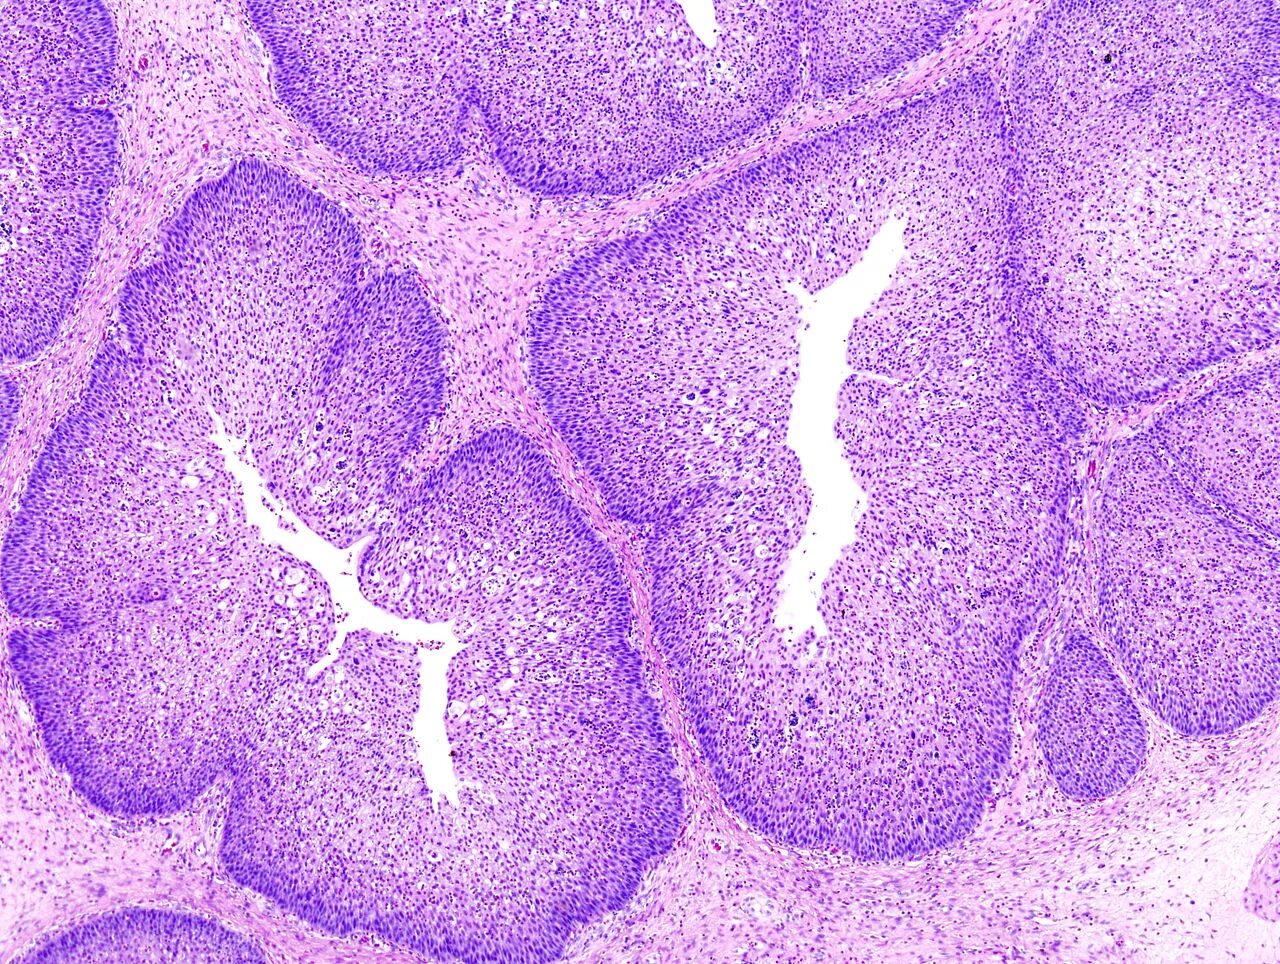

Папиллома гистология